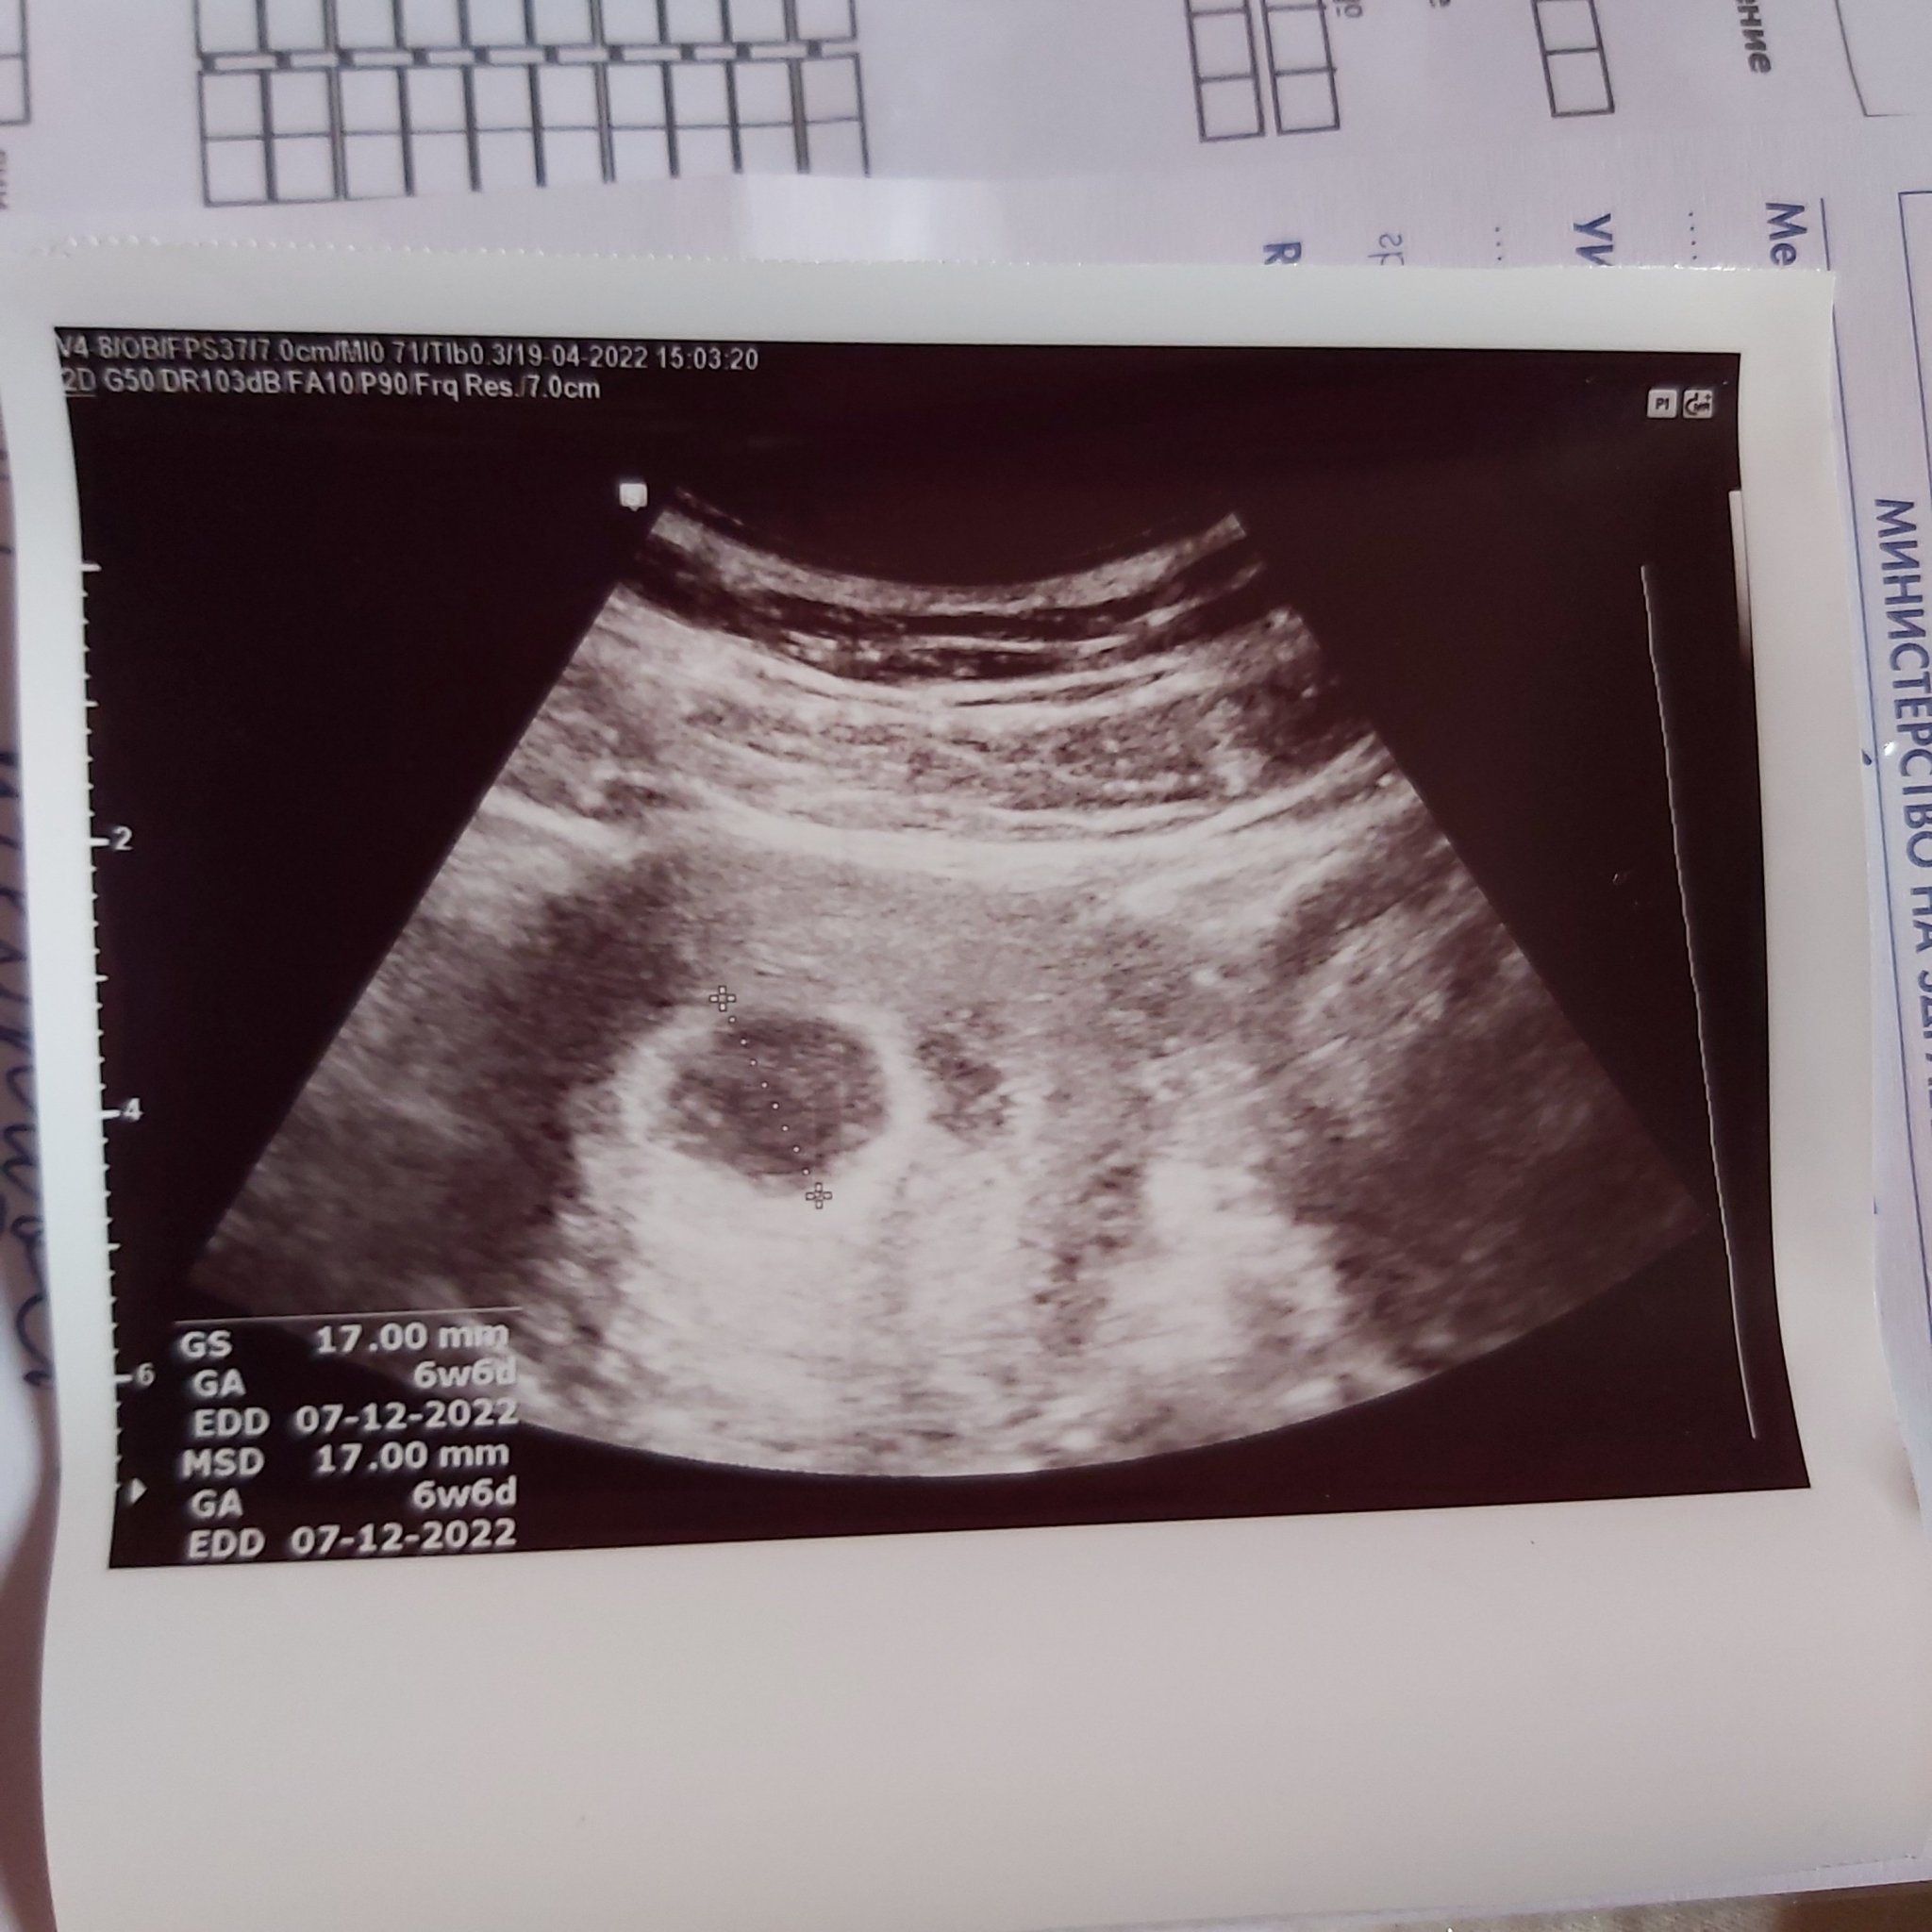

Кога за първи път усещат сърцето на бебето?